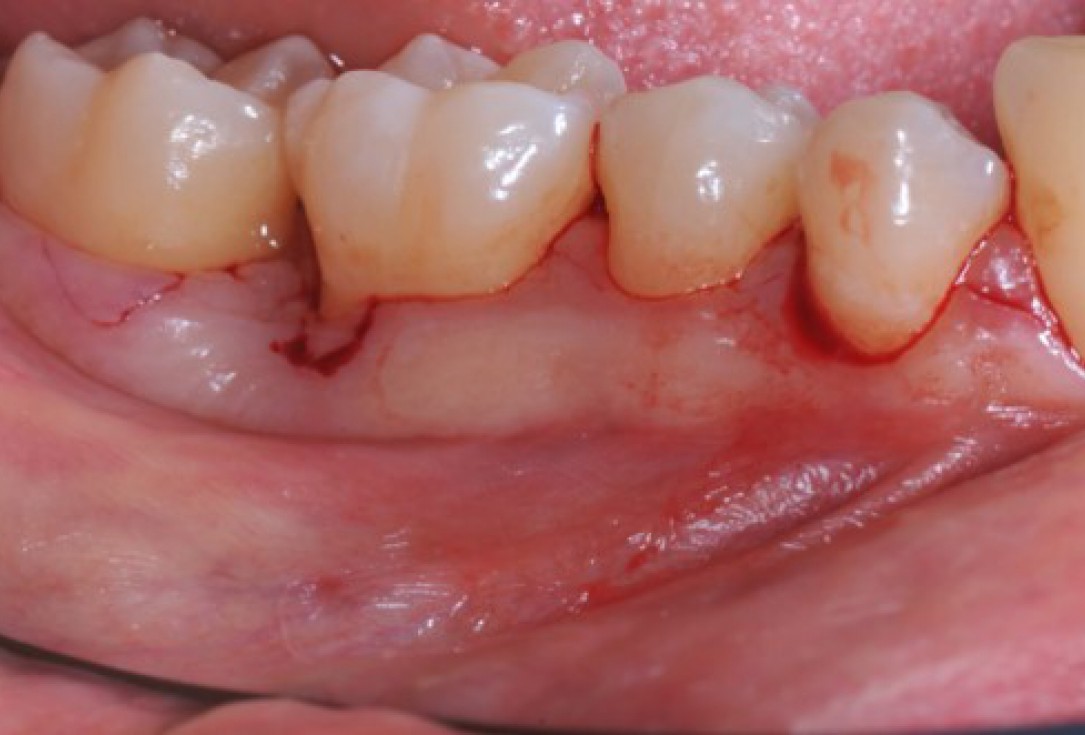

Pre-operative clinical situation. Shallow multiple adjacent gingival recessions in the first quadrant.